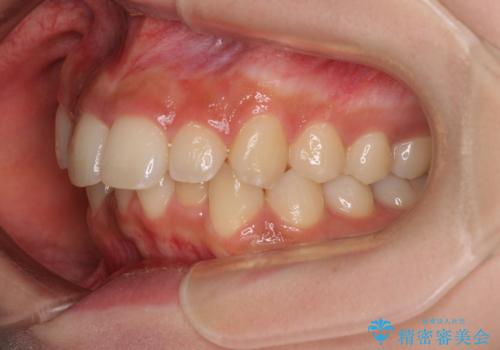

- 上顎前歯の突出感を気にして来院された患者様です。

上下左右第一小臼歯4本を抜歯して、積極的に口元を引っ込めるよう、ワイヤー装置にて矯正治療を行うこととしました。

抜歯矯正により、下唇が前方に突出した感覚が大幅に改善されました。